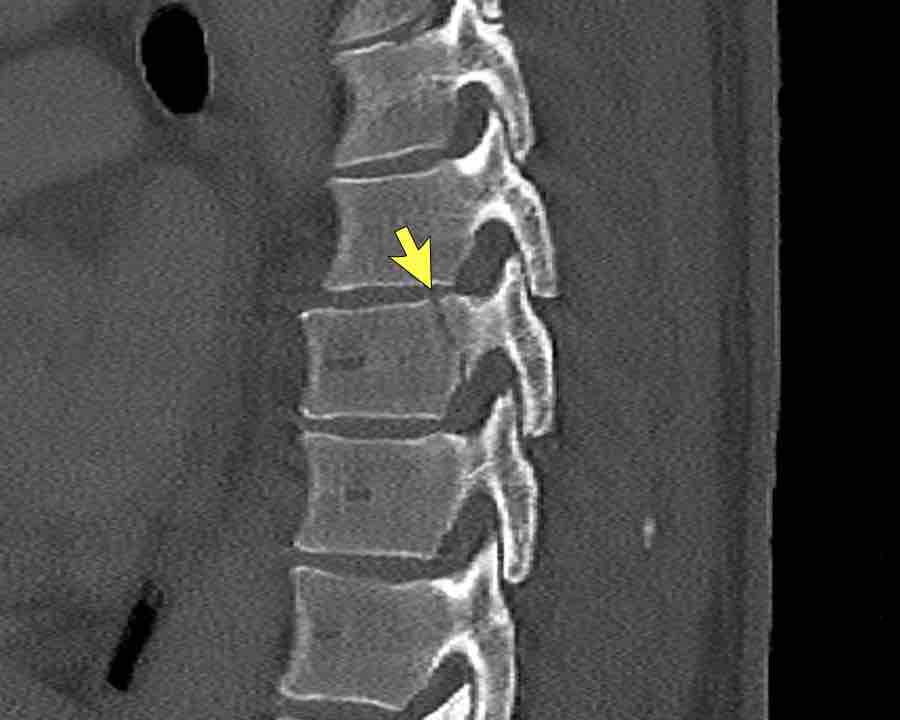

Scroll through the images.

What are the findings?

What is the highest AO-type of injury?

Findings

- Vertical fracture of the posterior border of the vertebral body. It looks a bit odd.

- Again we first have to look for the presence of a type C injury.

- Notice that there is a subtle posterior dislocation of the proximal levels. So this has to be C injury.

Conclusion

Injury type C + A3